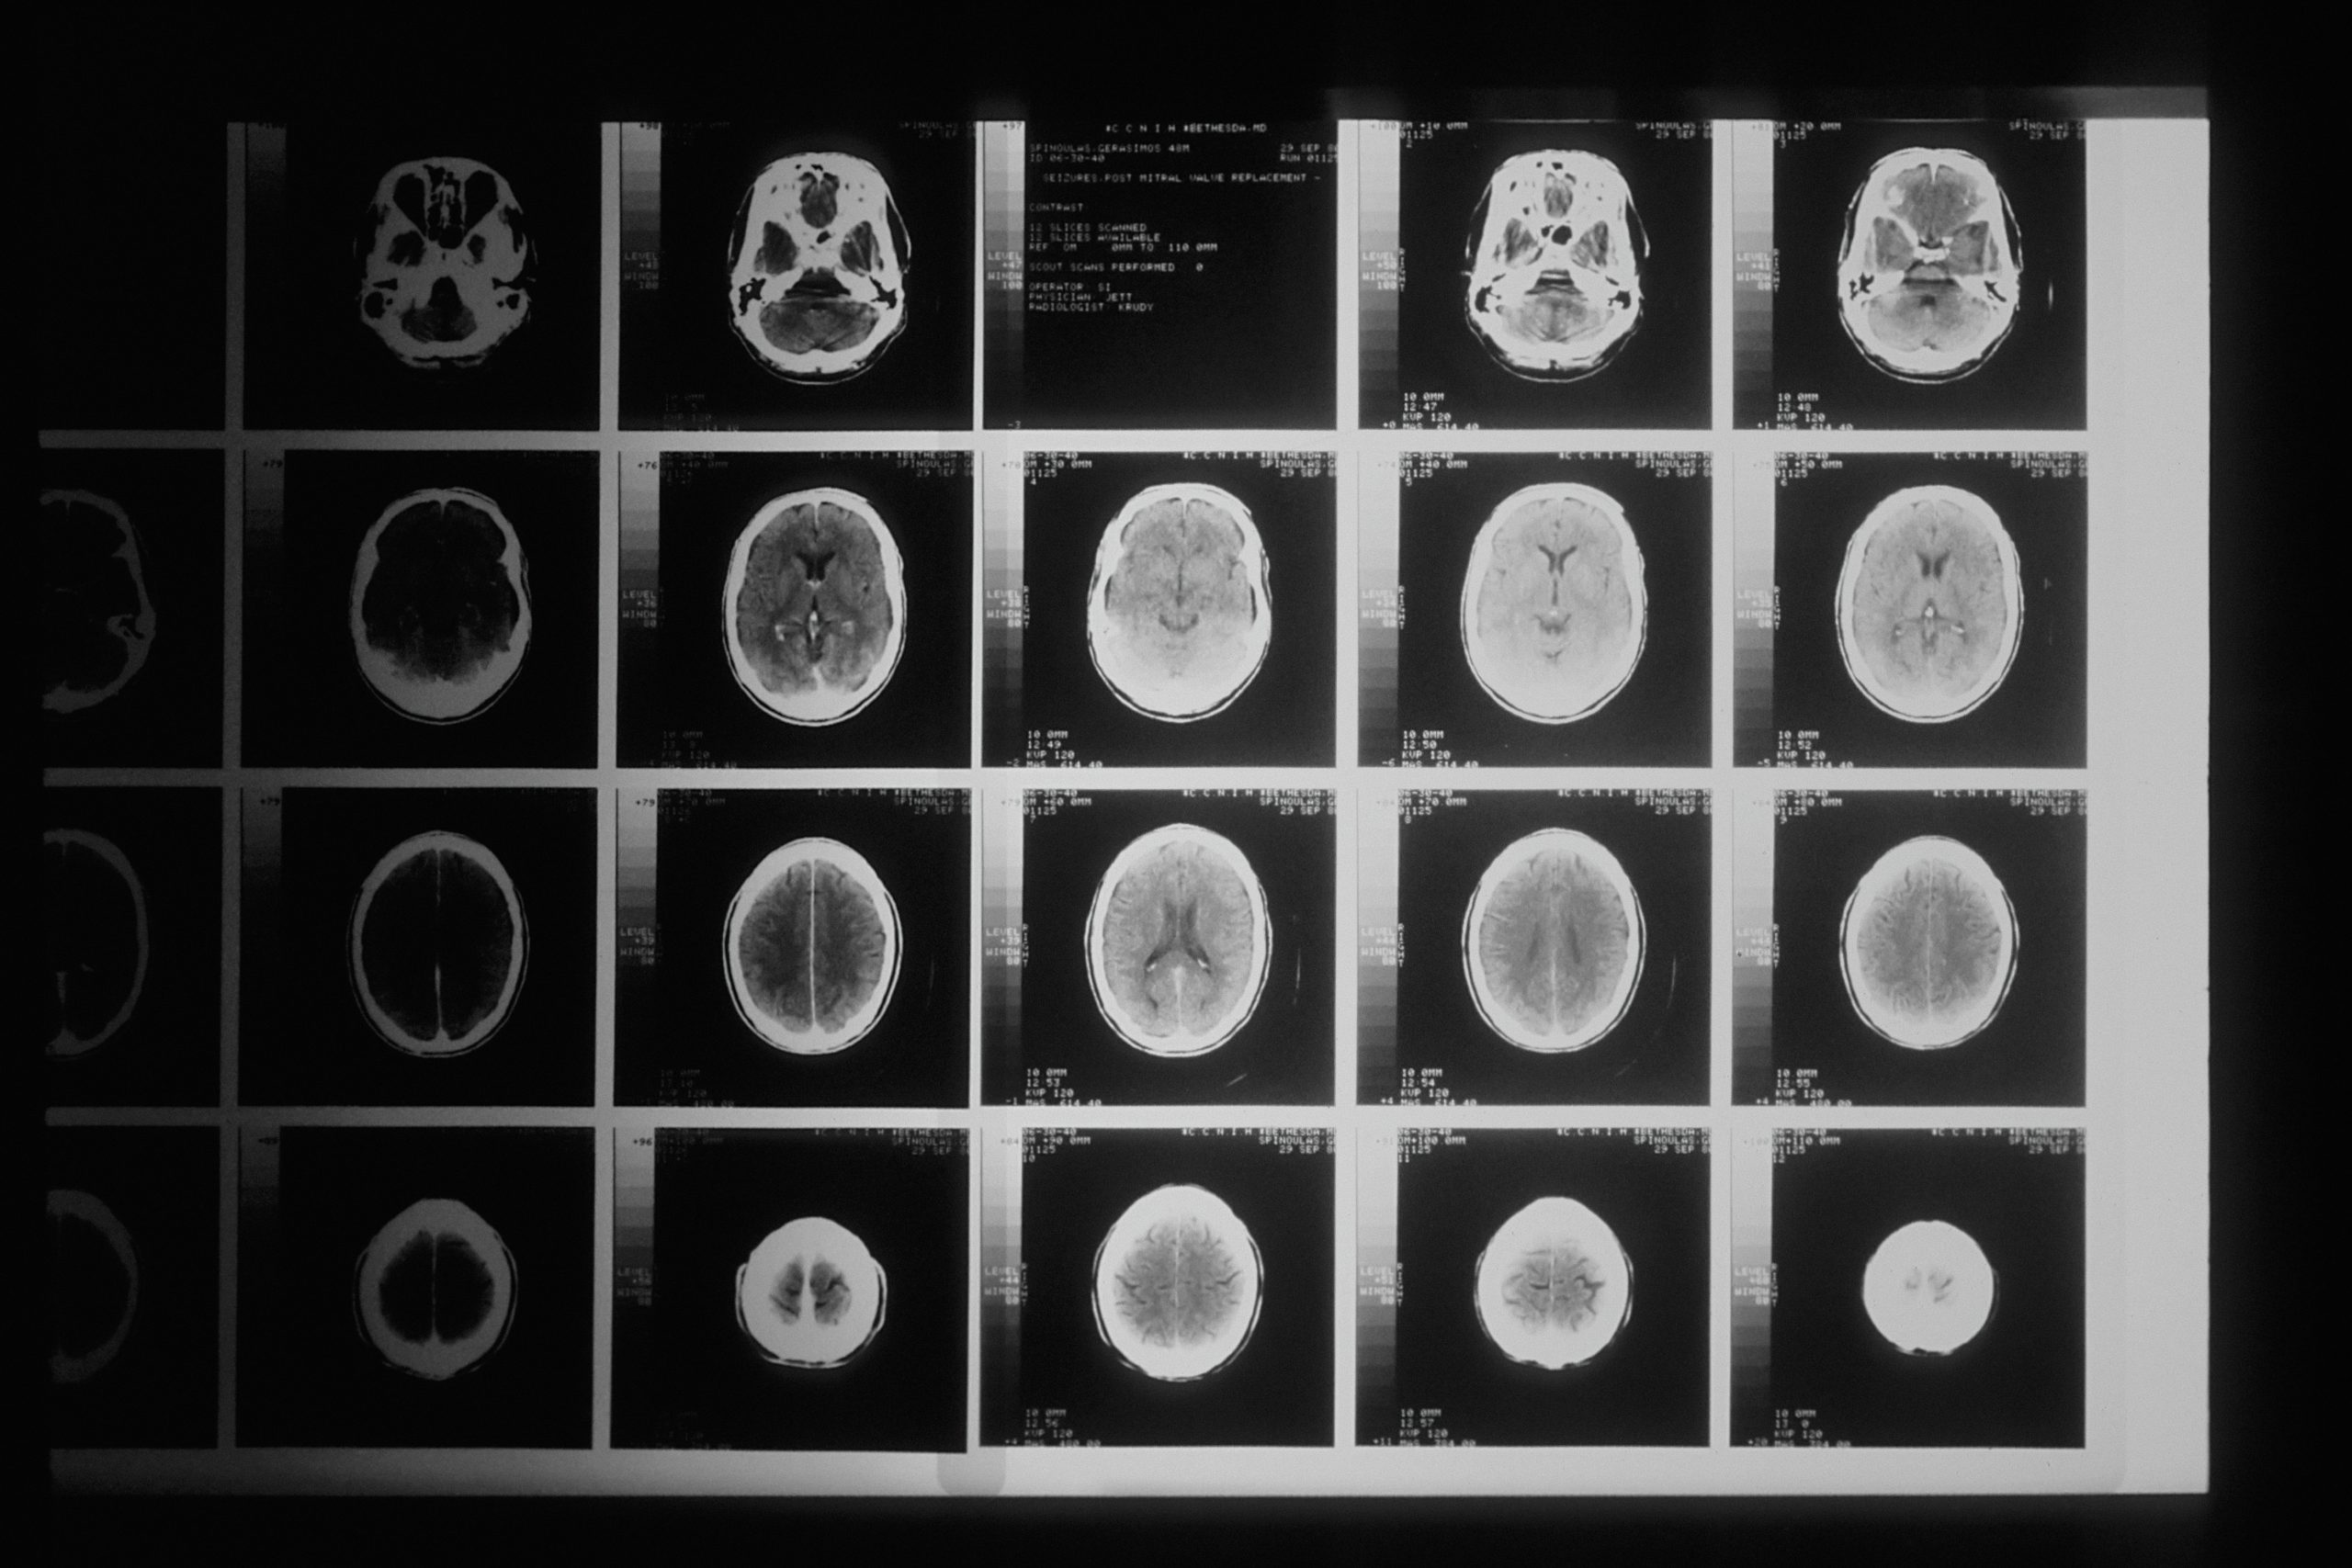

Dein Gehirn besteht aus rund 100 Milliarden Nervenzellen, die über 100 Billionen Synapsen miteinander kommunizieren. Diese Verbindungen werden ständig neu geknüpft oder abgebaut – abhängig davon, welche Gedanken und Muster Du oft wiederholst. Das ist Neuroplastizität, die Fähigkeit, dass sich Dein Gehirn anpasst und verändert.

Wissenschaftliche Untersuchungen zeigen, dass sich durch Achtsamkeit und Meditation die Hirnstruktur verändern kann:

- Der Mandelkern (Angstzentrum) schrumpft

- Der Hippocampus wächst

- Der Hormonspiegel verändert sich messbar

- Stress nimmt nachweisbar ab

- Denken beeinflusst die Struktur des Gehirns

- Bewusstes Umdenken kann neue Synapsen entstehen lassen